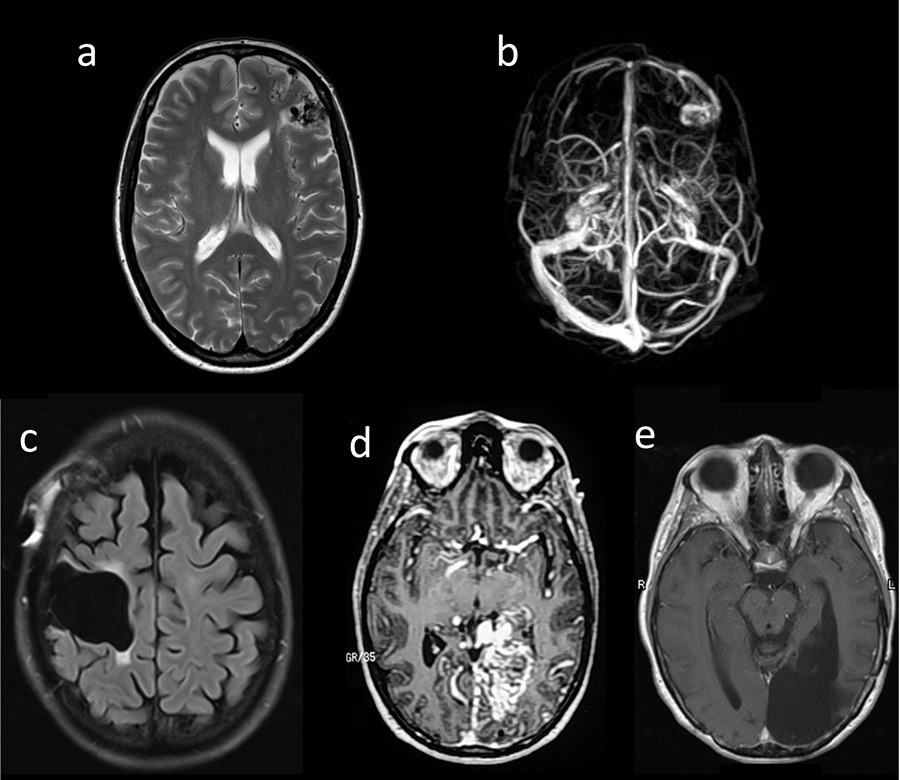

Figure 1

(a, b) Patient 1: T1-MRI (magnetic resonance imaging ) (a) and MRI-venogram (b); (c) Patient 2: MRI (FLAIR) after surgery; (d, e) Patient 3: MRI-angiography prior to surgery (d) and MRI (T1) after surgery (e).